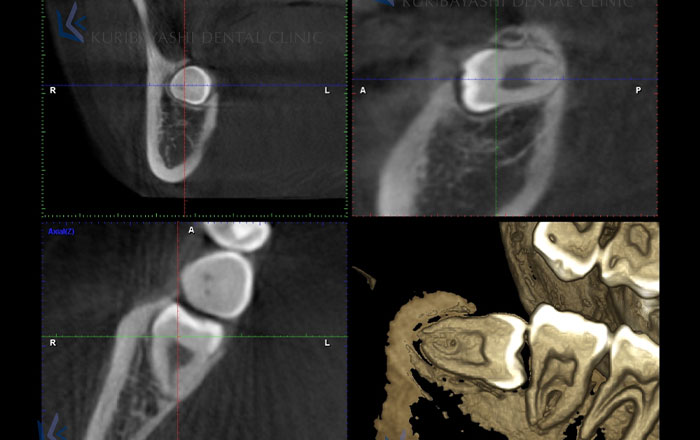

CTを使うことで、顎の部分を3次元の立体画像で撮影することができるため、より精度の高い審査・診断が可能になります。

そこで、X線の装置(CTなど)を使い、歯や骨の中を擬似的に輪切りにして、内側も見ることで、人体に物理的に傷をつけずに情報を得ることができます。

CTを使用すると、治療する上での大事な情報が色々分かります。

その際に必要な情報の、根っこの形はどうなっているか、根っこの曲がり具合はどうなっているか、歯の中の神経の本数は何本あるかなどを調べることができるので、より効率的に、治療の計画を立てることができます。

歯周病に関しては、歯周病によって、歯を支える骨がどれだけ溶けてしまっているかが分かります。

どの位置に、どのくらい骨の量が足りなくなっているかで、次の処置の判断がしやすくなります。

外科処置に関しては、根っこの先に膿が溜まっている場合、CTの画像に映るので、痛みの原因が調べやすくなります。

親知らず抜歯など、抜歯処置を行う場合にCT撮影を行うことで、歯の根っこと神経の近さを知ることができます。

抜歯時に、顎の中にある太い神経(下顎神経)と言われる部分を傷つけてしまうと、麻痺などの後遺症が出てしまう場合があるので、事前に検査が必要ですが、CT撮影ではそれを知ることができます。